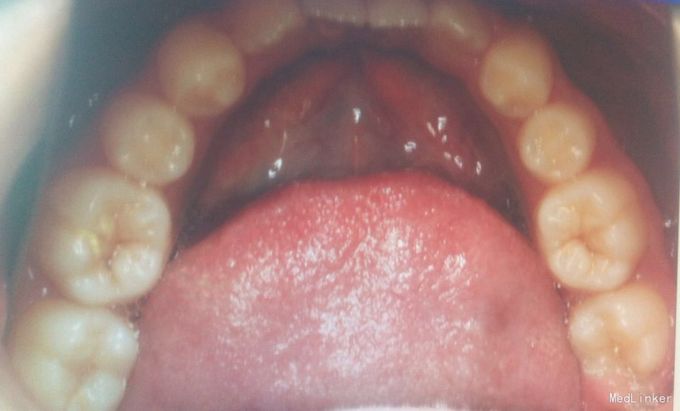

检查:恒牙期 右侧磨牙远中关系,左侧磨牙中性关系 前牙一度深覆合,正常覆盖 32、42未见 13、23唇侧错位 张口型异常 中线左偏约2mm 口腔卫生一般 X线未见32、42牙胚,28、38、48牙胚存在

诊断:安氏三类,先天缺牙 处理:拔牙矫治,直丝弓矫治器,拔除15、25,排齐整平上下牙列,关闭拔牙间隙,矫治后磨牙中性关系,前牙覆合覆盖正常,维持现有面型。